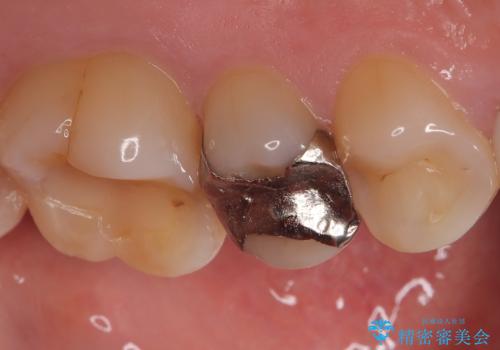

- 銀歯をやり替えたいとのことでした。残っている歯の量や長期的な予後をふまえ、患者様との相談の結果、被せ物での修復となりました。

メタルインレーを除去し、その下にあったう蝕を除去したうえで、CRにて築造を行い形成しました。印象時は圧排し、シリコンにて精密に行っています。